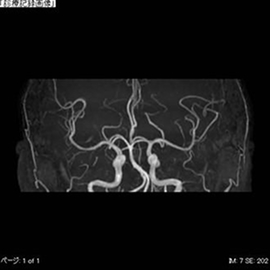

CTの検査画像例

MRI

PHILIPS社製Ingenia 1.5TMRIを使用しています。開口径が従来の装置より広いワイドボアタイプとなり、より圧迫感の少ない、患者さんに優しい検査環境を実現できます。また、世界初のデジタルコイルを採用しており、ノイズが少なく診断能の高い画像が得られるようになりました。